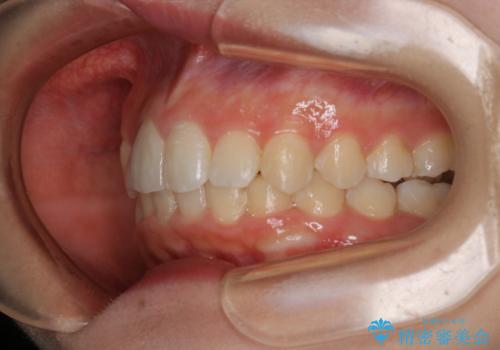

矯正治療でご自身の歯を移動して閉じることにしました。

また、咬んだときに下の前歯が隠れる過蓋咬合でしたが、矯正治療で改善しました。

右上の2番目の前歯が奥に入っている状態で、かぶせてあったため左に比べて短いセラミックになってしまっていました。

矯正治療で根の向きも修正したため、左右対称に審美的なセラミックを入れることができました。